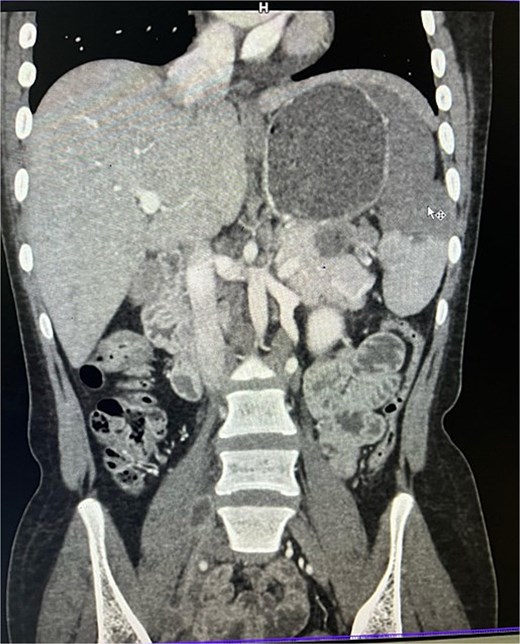

On imaging, ultrasonography showed a lobulated hypoechoic lesion in the region of the pancreatic tail and splenic hilum. This was very not conclusive, so a contrast-enhanced CT scan was planned, which revealed multiple necrotic, conglomerated lymph nodes (30 × 33 × 38 mm) near the splenic hilum and pancreatic tail, abutting the stomach and spleen, with maintained fat planes (Fig. 1). A splenic infarct involving a significant portion of the parenchyma was noted (Fig. 2), with multiple additional necrotic nodes along the retroperitoneum (paraaortic and iliac vessels) and mild pelvic free fluid. Then, CT-guided biopsy from the lymph nodal mass was planned, which showed moderately cellular smears showed caseous necrotic debris, lymphocytes, and clusters of epithelioid cells, suggestive of chronic necrotizing lesion consistent with TB.

CECT abdomen showing splenic infarct involving significant portion of splenic parenchyma—except at the lower pole of spleen.